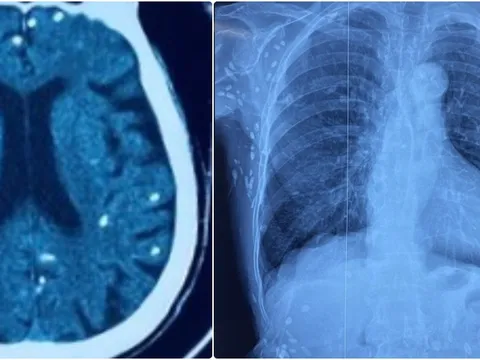

Rùng mình với hình ảnh nang sán dây lợn gây vôi hóa đầy cơ thể

Mặc dù không phát hiện ký sinh trùng sán dây lợn tại thời điểm bệnh nhân nhập viện, nhưng các bác sĩ phát hiện nhiều tổn thương ở não, dưới da vùng bụng ngực, ngực do nang sán dây lợn vôi hóa.